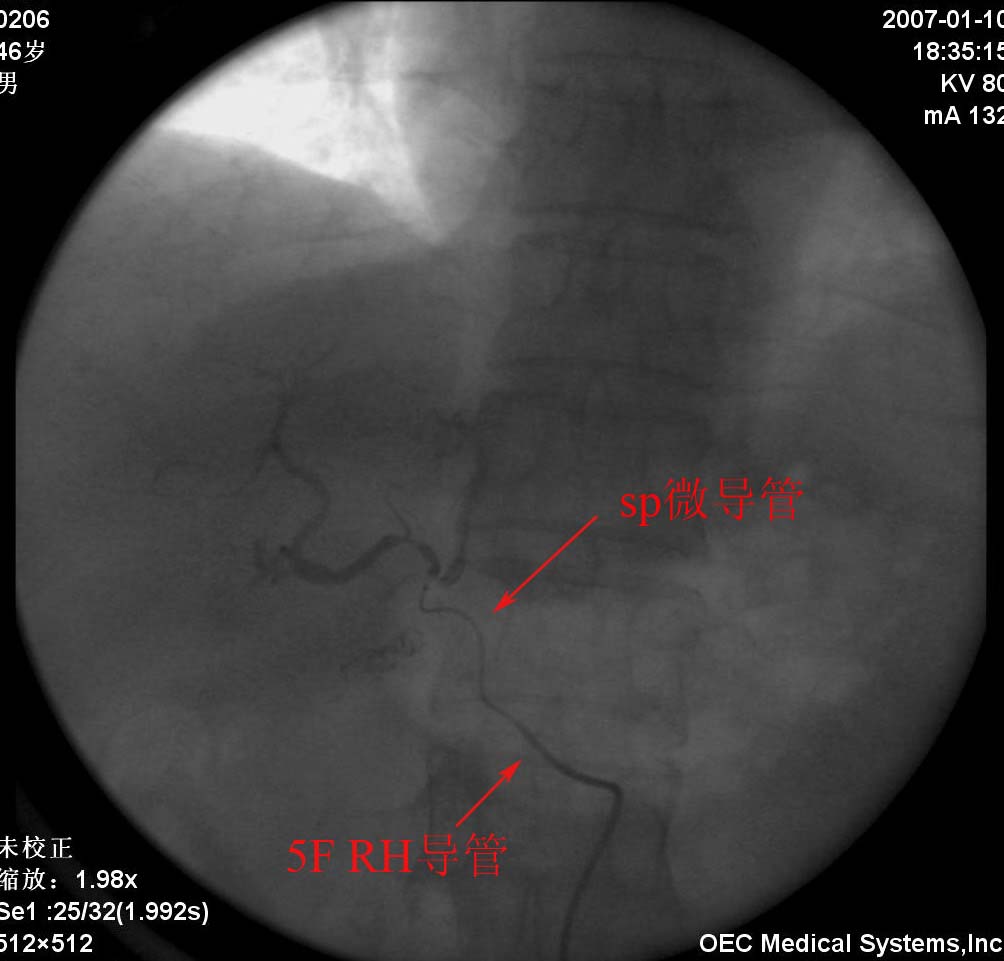

一般术后病人或多次tae后再介入治疗比较麻烦,此病人造影见肝固有动脉明显变细,分支减少(术后改变),肝左动脉呈直角从肝固有动脉发出,给超选择带来困难.可通过两种方法试解决.第1种就是楼主采用的方法,用钢圈或明胶海绵进行栓塞治疗.第二种就是采用3fsp微导管超选择治疗.两种方法相比第一种更经济。

此病例采用了微导管,由于胃十二指肠动脉与肝左动脉相隔很近,肝内血管分支又很细小,故出现释放碘化油时返流明显,因而采取了胃十二指肠动脉栓塞.